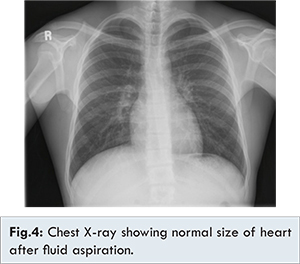

After the fluid aspiration the patient symptoms improved, dyspnoea was reduced. A repeat X-ray had showed the size of the heart had decreased [Fig.4]. The patient was then started with thyroxine 200 µg/day. The patient came for follow up at the end of 1 month and the patient was totally free of symptoms and she is doing well.